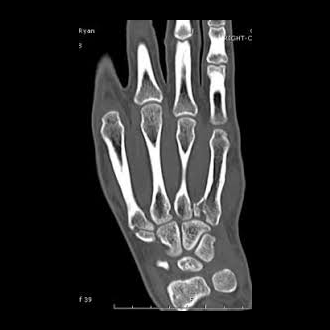

A CT scan is an x-ray procedure that is enhanced by a computer and gives out a three-dimensional view (referred to as a “slice”) of a particular part of the body.

While dense tissue can block some areas during standard x-ray image procedures, CT scans create a three-dimensional view by using a computer to combine different slices, showing all bone and tissue.